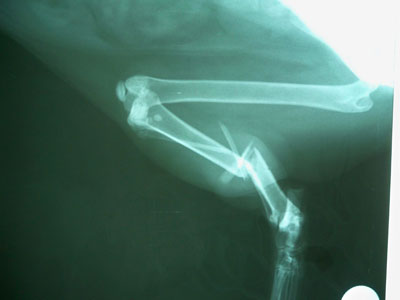

Γάτος 12 μηνών με συντριπτικό κάταγμα μεσότητας κνήμης και κάταγμα περόνης. Παλαιότητα κατάγματος περίπου 2 βδομάδες. Έγινε ανάταξη των 2 μικρών κομματιών με 2 σύρματα. Ακολούθησε ανάταξη των καταγματικών άκρων με πλάκα 2.7mm. Τοποθετήθηκαν 5 κοχλίες στο κεντρικό κομμάτι και 3 στο περιφερικό (2.7mm).

Χειρουργοί : Πούπαλος Γιώργος, Σιδεράς Δημήτρης